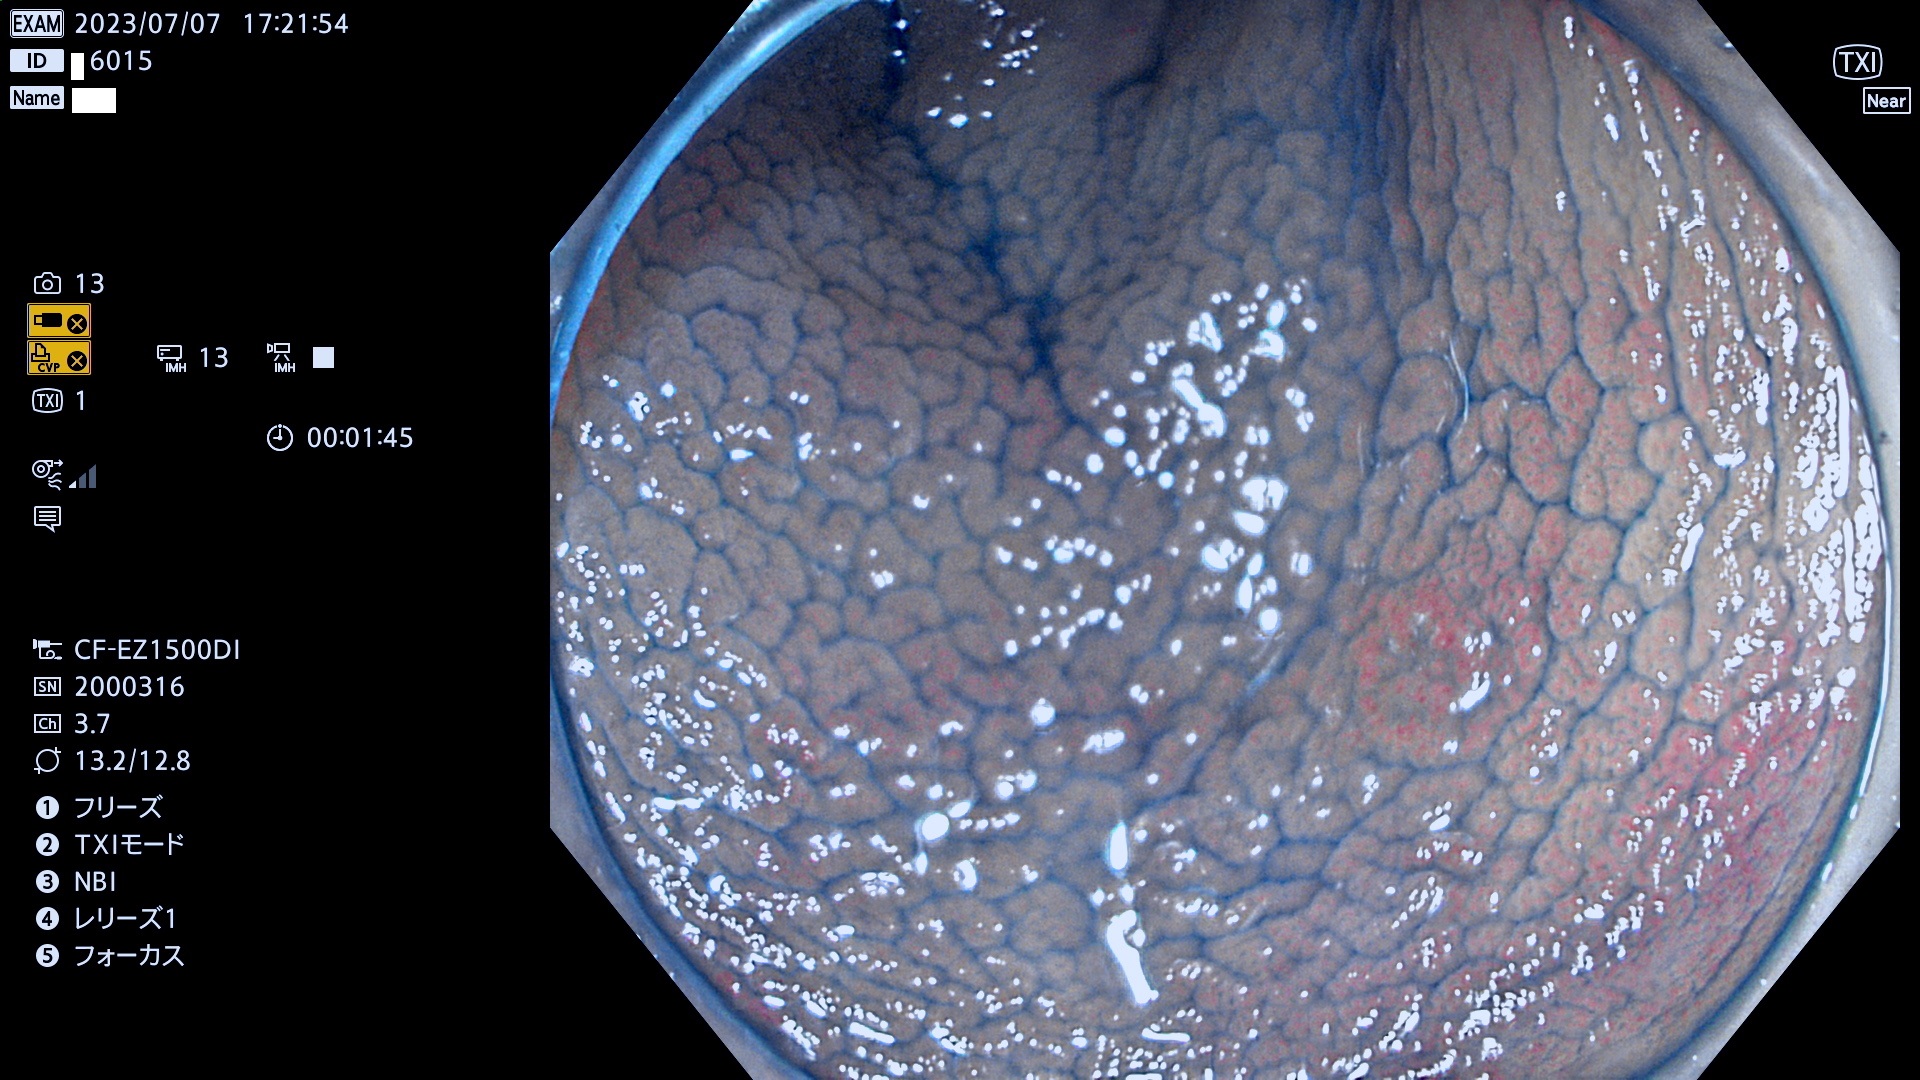

大腸Ub、Uc型・腺腫とは?

「表面型腺腫(Flat Adenoma)の中で、完全に平坦な物をUb、陥凹している物をUcと呼びます。平坦隆起型(Ua)よりも、発見が難しく危険な病変です。このタイプの発見率は「腺腫発見率」よりも、遥かに重要な意義があります。

抽出の対象期間 2023年7月6日(木)〜7月9(日)の4日間(48件の検査)6件